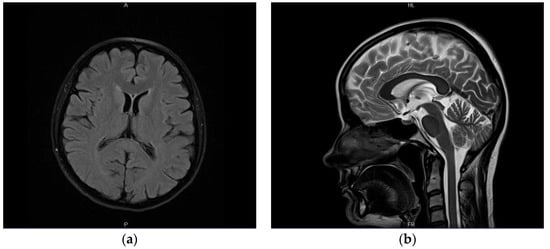

A previously healthy female patient, age 41, reported to the emergency unit (June 2019) due to recurrent episodes (2–3× per week) of severe headache and collapse. She mentioned first symptoms occurring a month before admission (May 2019). No abnormalities were observed in neurological examination or brain computed tomography (CT) at the time (Figure 1a). Outpatient MRI examination was performed 2 months afterwards (August 2019), which revealed no relevant findings apart from a small (size < 1 cm) focal lesion, consistent with a meningioma of the right parietal region (Figure 1b). Next, the patient underwent electroencephalography (EEG) in October 2019, which indicated secondary generalized seizures originating bilaterally in the temporal lobes. Based on the clinical image, the patient was diagnosed with structural epilepsy and received outpatient treatment (400 mg carbamazepine twice daily). As the treatment was poorly tolerated by the patient, who felt weak, generally unwell, and reported worsening headaches as well as repeated episodes of collapse, a decision was made to substitute carbamazepine with lamotrigine (100 mg twice daily). No symptom alleviation was observed. In fact, the patient reported intensification of headache and general weakness. The drug was discontinued (beginning of June 2020). Due to repeated episodes of collapse, a cardiological consultation was made which excluded cardiogenic causes of the clinical image. The patient observed further exacerbation of clinical symptoms: headaches appeared on a daily basis; the patient collapsed with an average frequency of four times per month (with brief loss of consciousness at times); no convulsions or involuntary urination were present. Apart from hypoesthesia on the left side of the body, confirmed by neurological examination, no other abnormalities were found at the time.

Figure 1.

(a) Normal brain image—CT examination in native phase; (b) contrast-enhanced T1-weighted axial MR cross-section indicating a small right parietal meningioma (arrow).